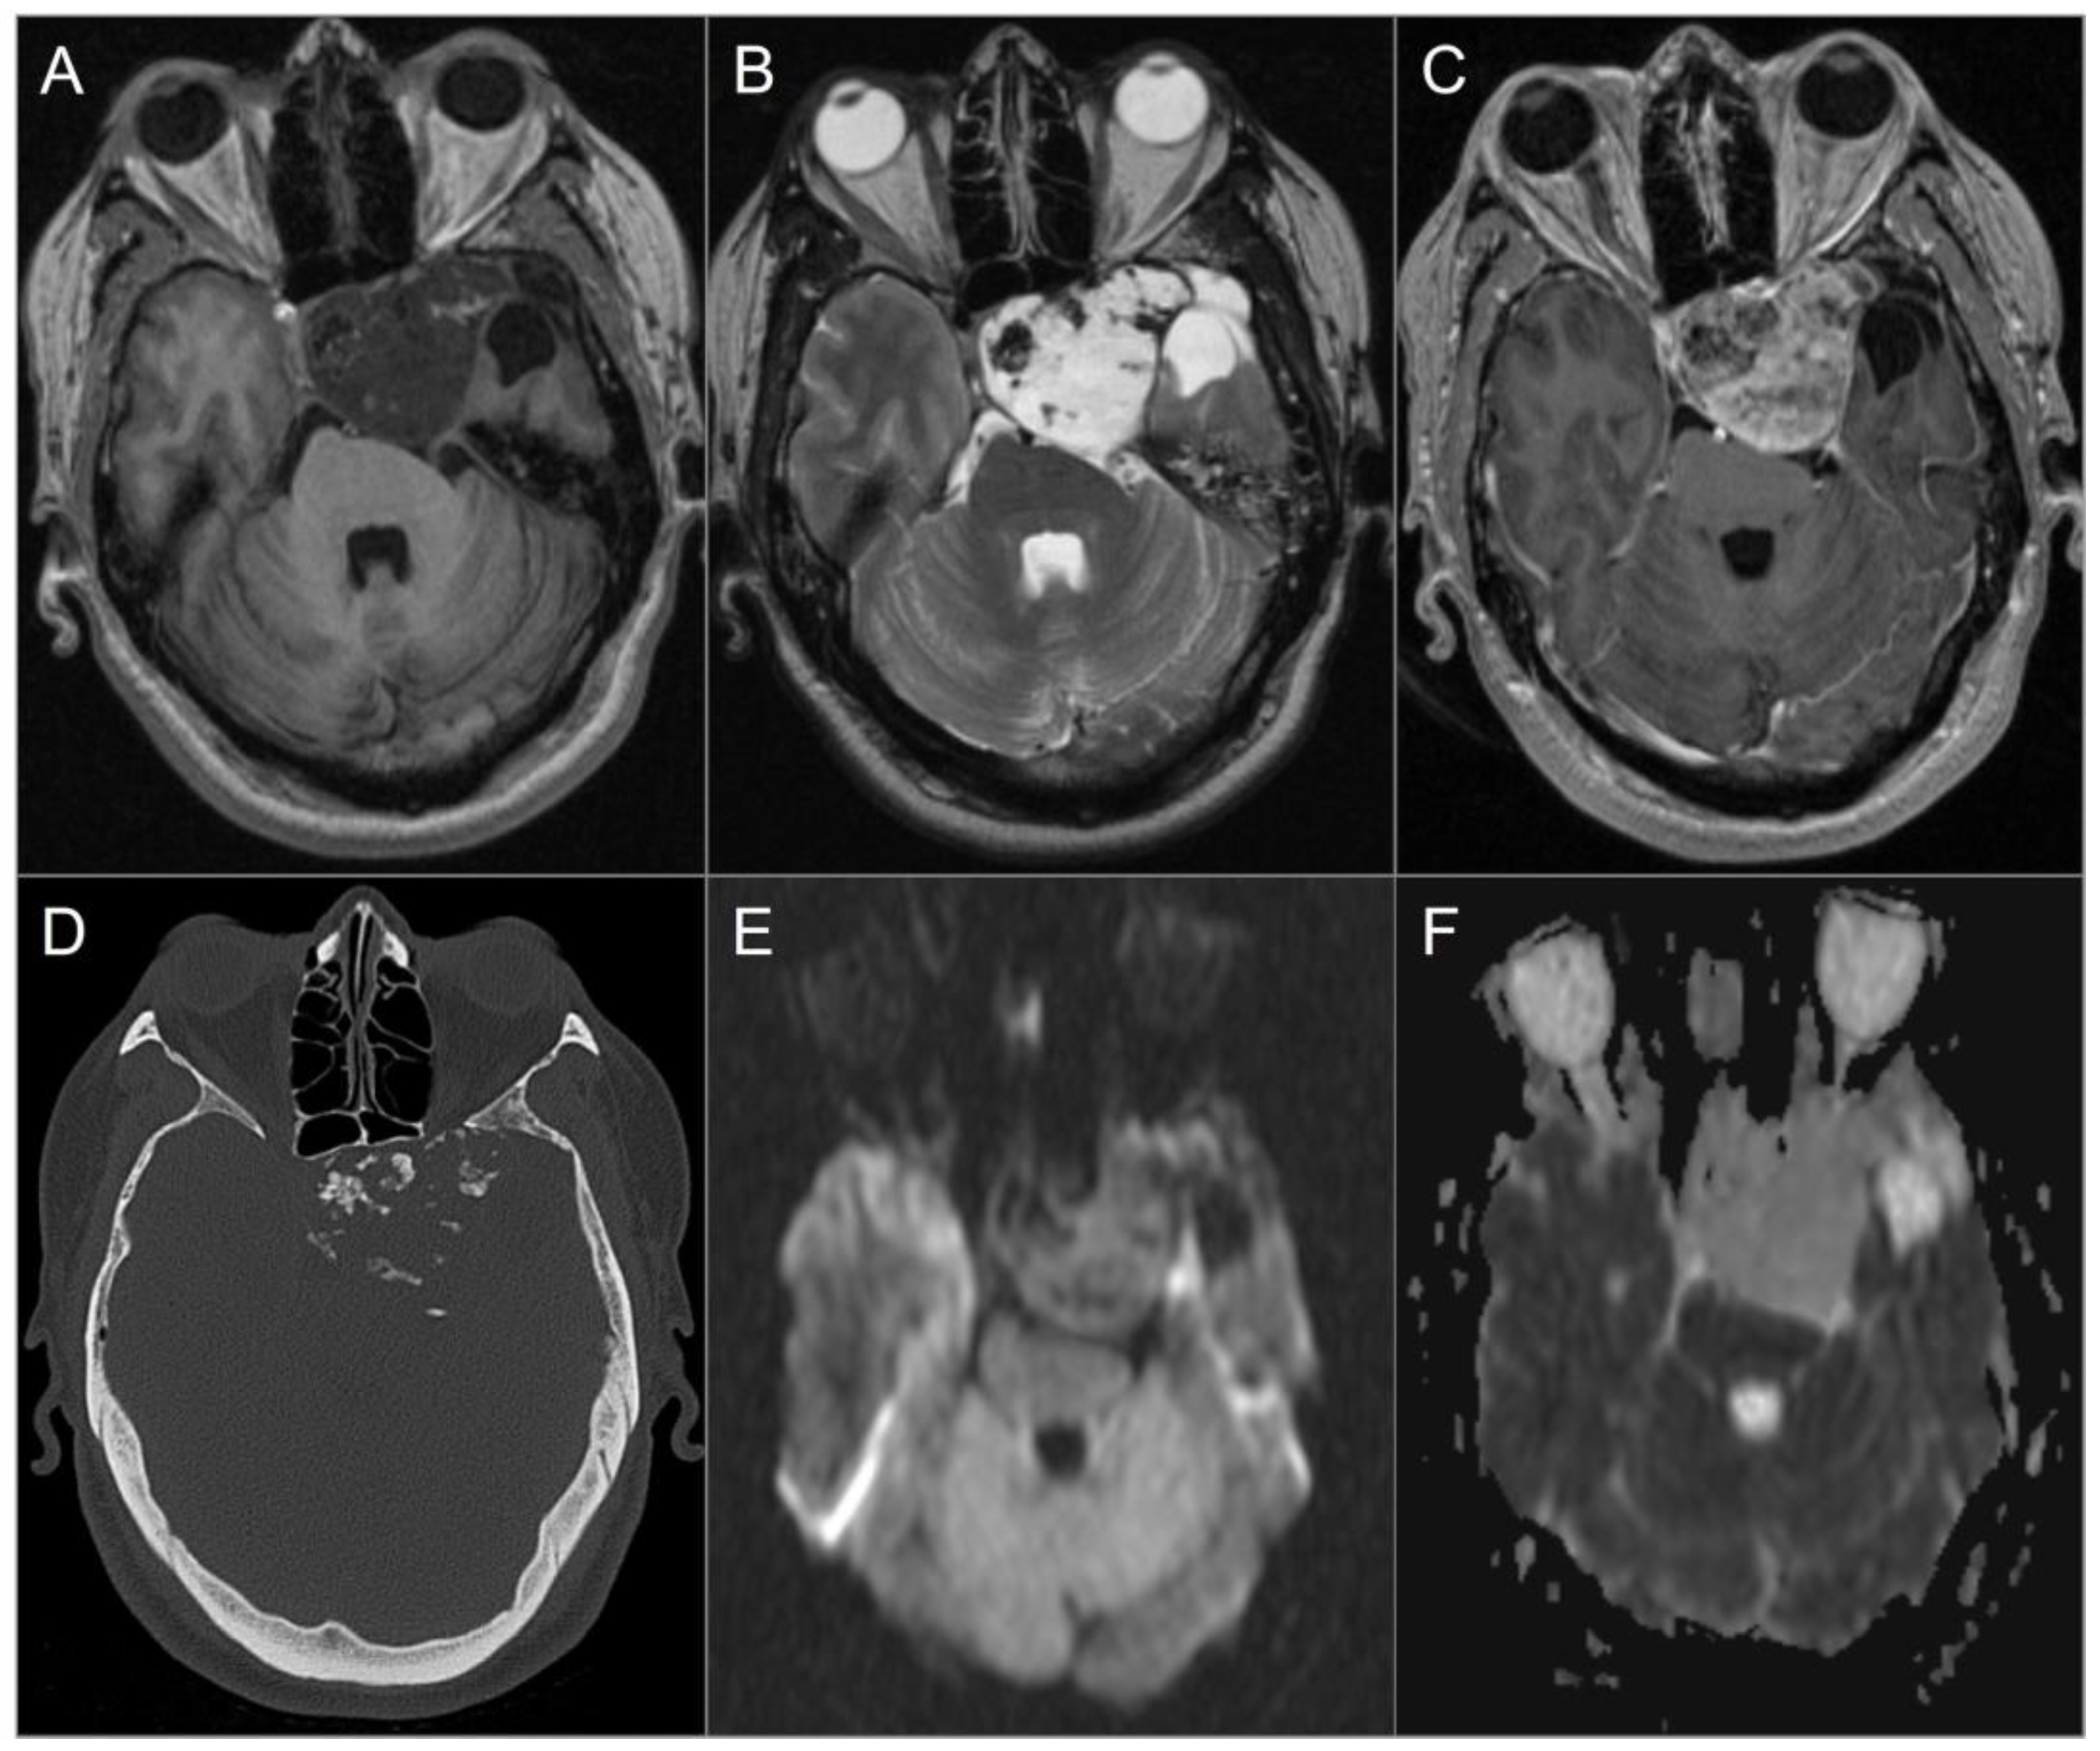

4.4.5. Paraganglioma